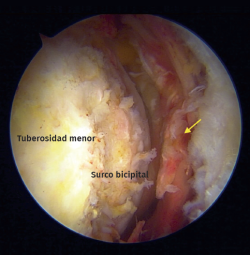

Durante el periodo descrito, se intervino a un total de 15 pacientes que cumplían con los criterios de inclusión. Se excluyó a un paciente debido a que el tiempo de seguimiento era insuficiente. Se incluyeron un total de 14 pacientes (Tabla 1), con una edad promedio de 65 años (rango de 46 a 76 años), 8 de los cuales eran hombres (57%). El tiempo promedio de seguimiento fue de 29,4 meses (rango de 24 a 41 meses). De los 14 pacientes evaluados, 13 (92,8%) presentaban algún compromiso del bíceps proximal como roturas parciales, lesiones degenerativas o inestabilidad medial (Figura 5). Se realizó una tenotomía del bíceps en 9 pacientes (64,2%), una tenodesis intraarticular en 2 casos (14,2%) y se detectó una rotura crónica del bíceps en 2 pacientes (14,2%). En la mitad de los pacientes (7) la rotura subescapular se reparó con 2 anclajes con nudo y en los restantes, con una fijación híbrida utilizando un anclaje superior con nudo y un anclaje inferior sin nudo con cintas de sutura (Tabla 2).

Figura 2. Vista artroscópica desde el portal anterolateral en un hombro derecho en posición de silla de playa. Rotura crónica del tendón del bíceps. Flecha: espesor total y retracción del tendón subescapular.

Figura 5. Vista artroscópica. Rotura completa del subescapular con inestabilidad medial de la cabeza larga del tendón del bíceps. Asterisco: tendón del bíceps. Flecha: rotura del tendón subescapular.